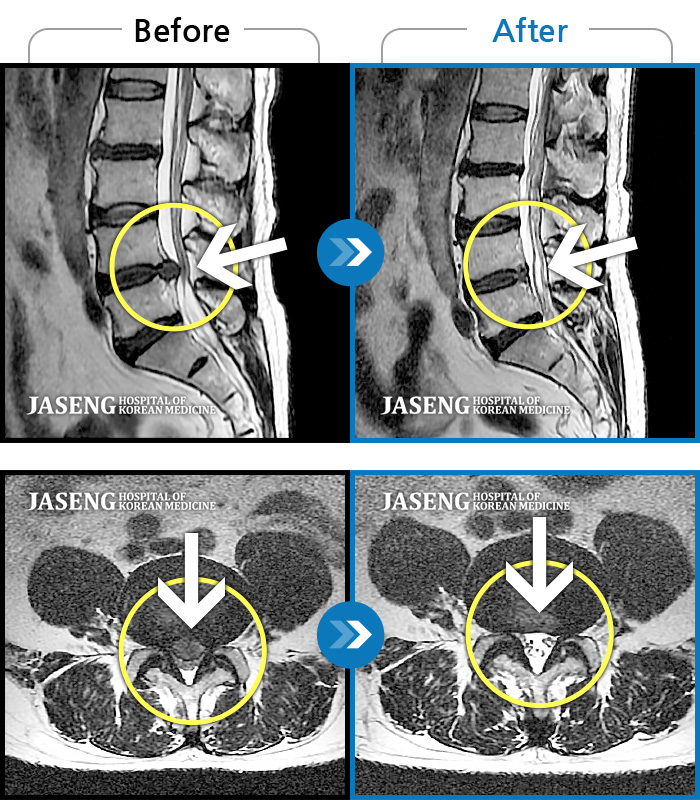

허리디스크

안산 · 김민수 원장

허리가 아프고 두 다리가 저려서 조금만 걸어도 주저 앉아야 했습니다.

촬영시기

2018.12.20 ~ 2023.02.21

2023.02.24